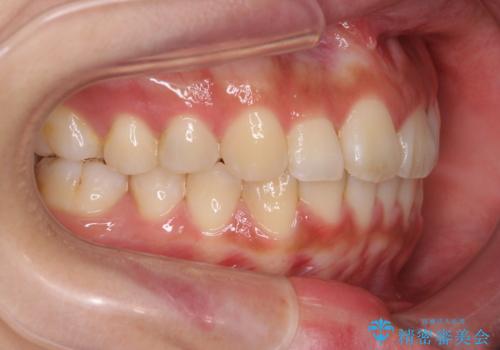

- 前歯の目立つねじれを矯正治療で治したい、と来院されました。

マウスピース矯正を始める前に、ねじれを取るのが短期間で済む部分ワイヤー小矯正を行うことで、全体的な治療期間を短くする治療計画を実行していきます。

前歯のねじれはマウスピース矯正の苦手な動きになり、治療期間が長くなる原因になりやすいです。